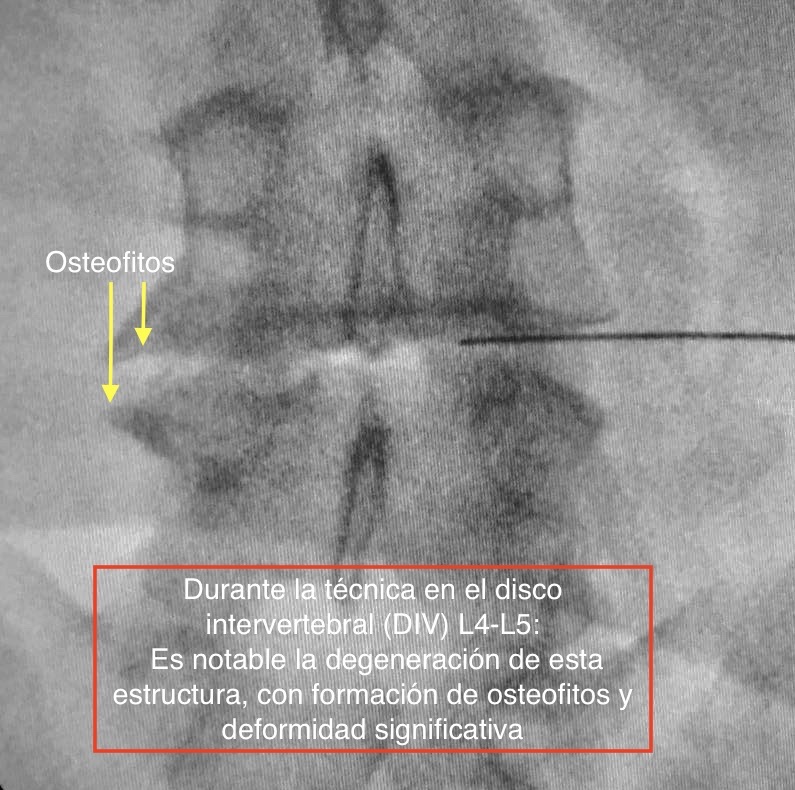

La TERÀPIA REGENERATIVA NEUROESPINAL, desenvolupada per l'equip de Neurocirurgia de la Clínica del Remei (COT- Neurocirurgia Remei) i dirigida per la Dra. Ivón González Valcárcel, és una Intervenció nova i mínimament invasiva exempta de reaccions adverses, avalada per evidència científica, que utilitza la biotecnologia. Ens brinda beneficis immediats en el control del Dolor Lumbar, així com ofereix efectivitat en revertir la cascada degenerativa, amb la conseqüent REPARACIÓ i REGENERACIÓ del disc intervertebral i altres teixits afectats.

Els factors de creixement plaquetaris són proteïnes que es troben en la nostra pròpia sang, exercint importants efectes biològics. Mitjançant aquesta revolucionària tècnica, som capaços de activar-los, concentrar-los i infiltrar amb alta precisió a la zona danyada per la patologia degenerativa. Així participaran directament en la regulació del DOLOR i en la REGENERACIÓ, mitjançant l'estimulació de funcions que donen lloc a la millora significativa o, fins i tot, a la desaparició dels símptomes amb ràpid retorn a l'activitat física quotidiana, amb la qual cosa és una excel·lent alternativa a la cirurgia convencional en molts dels casos